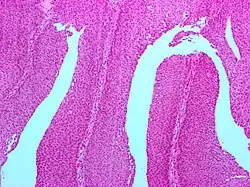

| Micrograph of a PUNLMP. Intermediate magnification. H&E stain. | |

Papillary urothelial neoplasm of low malignant potential (PUNLMP) is an exophytic (outward growing), (microscopically) nipple-shaped (or papillary) pre-malignant growth of the lining of the upper genitourinary tract (the urothelium), which includes the renal pelvis, ureters, urinary bladder and part of the urethra.

Histologically, they have a papillary architecture with slender fibro vascular cores and rare basal mitoses. The papillae rarely fuse and uncommonly branch. Cytologically, they have uniform nuclear enlargement.